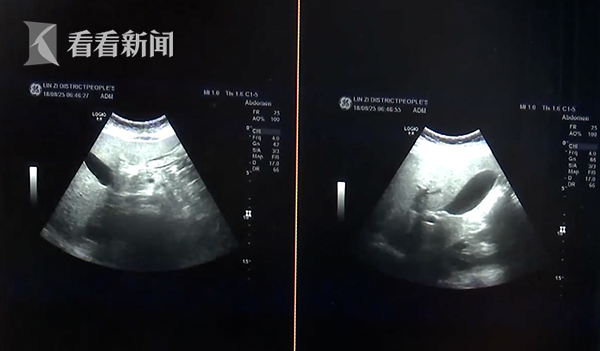

不久前,淄博一位6岁的男孩感冒发高烧,到了医院一检查,却发现他有一项转氨酶的指标高出标准三倍多,最后被确诊为了脂肪肝。

临淄区人民医院儿科二病区主治医师王洪敏:“他当时并没有像成人脂肪肝表现出恶心、厌油、食欲下降,等一些典型的表现,当时是我们通过化验血做超生才发现了脂肪肝的情况,所以说儿童脂肪肝的表现早期是很不典型的,需要我们家长早期提高警惕。”

医生说,六岁已经是他们收到患脂肪肝最小的病例了。原来,这个孩子最喜欢吃炸薯条、炸鸡等油炸食品,还天天喝可乐等含糖量高的碳酸饮料,又不爱运动,导致身体肥胖。医生说,很可能就是这些生活习惯,引发的脂肪肝。